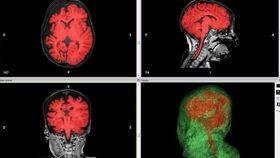

Given the complexity of the procedure, the medics decided to first create an exact replica of Mandeville's brain to use in a practice run. The model was produced by the Simulator Program at Boston Children’s Hospital using scans of the child’s brain. It was printed with soft plastic and with a precision of 16 microns per layer, according to The Verge. Blood vessels were even printed in different colors so that they could be spotted easily. According to Dr. Joseph Madsen, director of the epilepsy program at the hospital, surgeons can examine, cut and manipulate the models.

As before, a 3D-printed model of the infant’s brain was produced from CT scans and used both before and during the surgery as a guide for the surgeons. Once again, the surgery was successful.